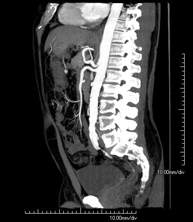

- Abdominal aorta CT angiography

A non-invasive diagnostic test that involves studying the abdominal aorta by obtaining high-definition anatomical images using CT (computed tomography) equipment and iodinated contrast. With the aid of workstations specialised for arterial studies, the image quality supports 2D and 3D reconstructions. It is indicated in patients with vascular disease (atherosclerosis), aortic aneurysms, abdominal pain of possible vascular origin, pre-surgical studies of lesions adjacent to the abdominal aorta as a vascular ‘map’, etc. Information obtained non-invasively is indispensable for patients requiring percutaneous or surgical processing. In patients who only require tracking of vascular lesions, this technique is the non-invasive technique of choice, together with MRI angiography.